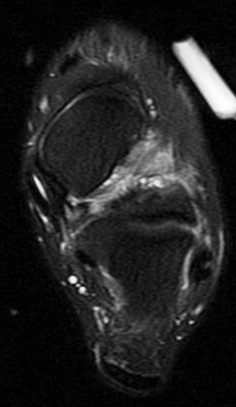

36 yo M s/p ankle sprain 7 months ago

Marked edema and scarring in the tarsal sinus. Has healed sprains of the ankle ligaments with scar remodeling (not shown). You can see where the ongoing pain is by the oil marker. I insist on having pain markers when possible. Reference article.

sinus tarsi syndrome ( RID3222 )